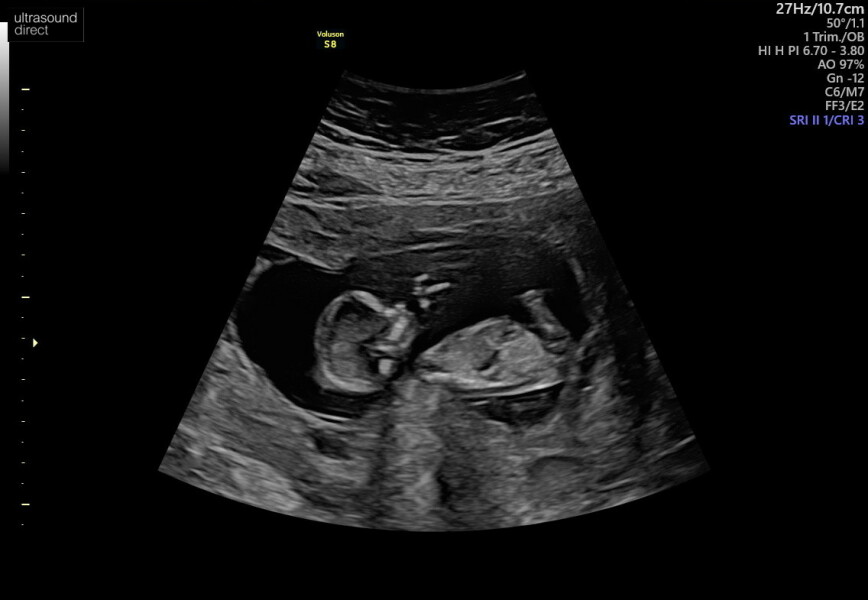

I'm 13 weeks now and have my scan tomorrow, fingers crossed for good news 🤞

I had my scan today 🥰 baby was so active! New due date 17th July.